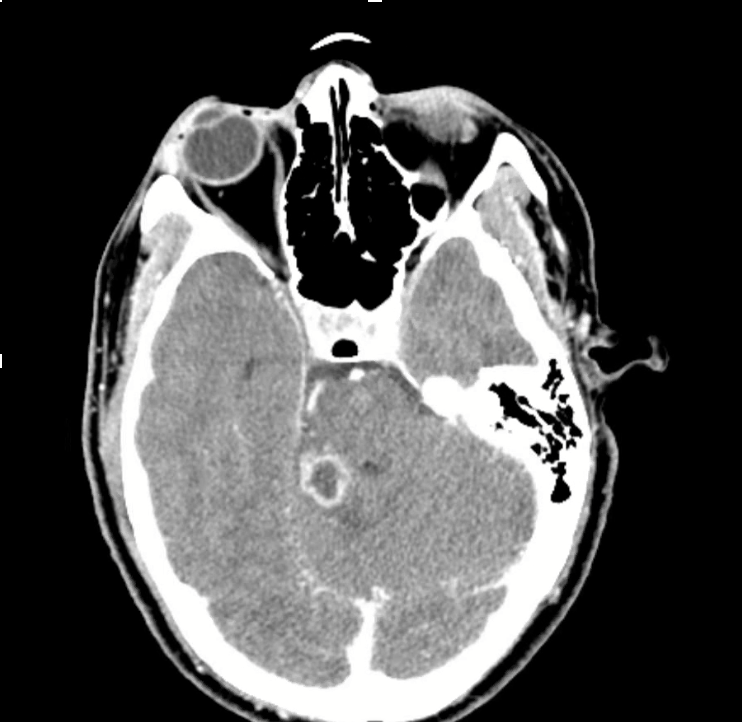

3) Neuro findings—ring-enhancing lesions

- Differential: septic emboli/abscess, nocardia, fungal, TB, parasites, metastases, vasculitis, sarcoid.

- Partner with neuroradiology for pattern nuances; treat seizures but keep searching for the unifying diagnosis.

- Therapy: Targeted TKI (crizotinib) → dramatic radiographic response of miliary lung disease and CNS lesions.

- Teaching point: even “miliary TB-like” lungs + CNS lesions in a 20-something can be driver-positive lung cancer—don’t let age or pattern blind you.